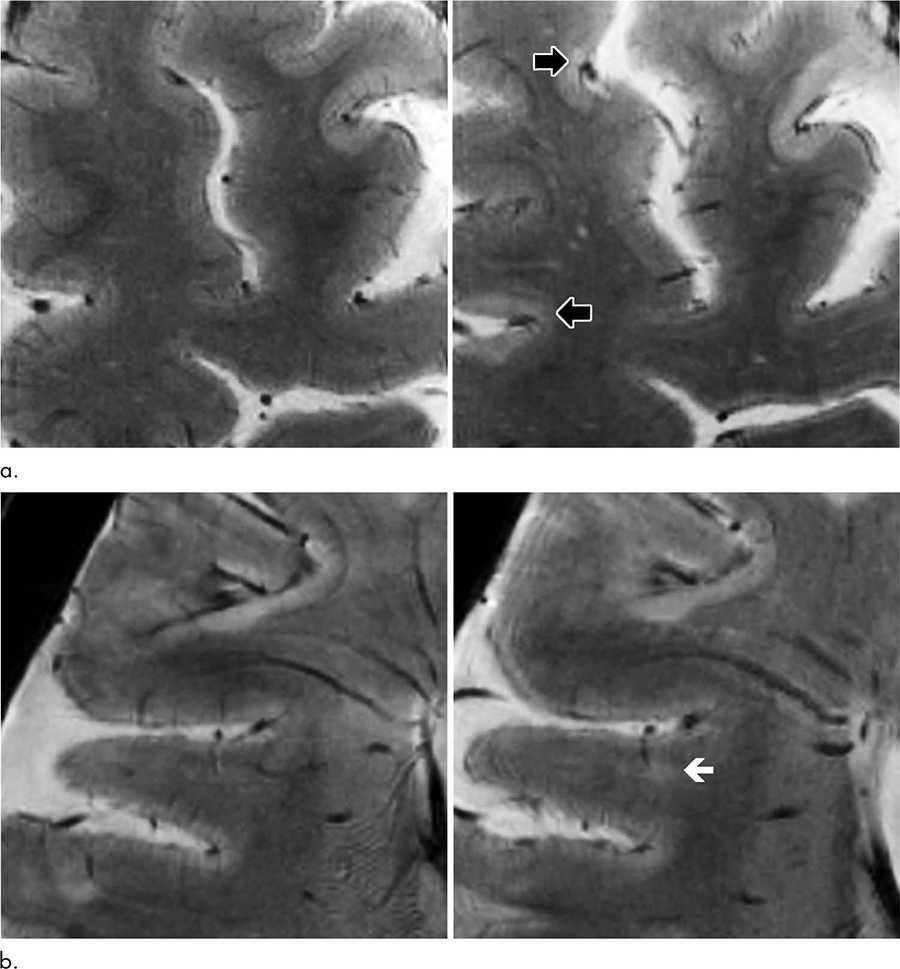

MS was once considered a disease of the brain’s white matter, but recent research has shown that cortical lesions develop even earlier in the course of the disease. These lesions are not easy to see with conventional-strength MRI. For the new study, researchers tracked MS patients using a 7-Tesla (T) MRI scanner.

The 7T brain scans showed that the cortical lesions tended to accumulate in the sulci.

While the reasons for the accumulation of lesions in the sulci are not definitively known, researchers note that the flow of cerebrospinal fluid is likely to be restricted there. The restricted flow might make the sulci more vulnerable to inflammatory responses.